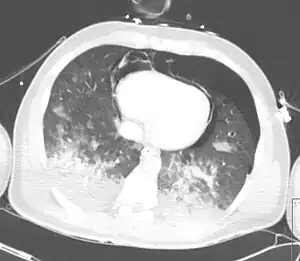

Computed tomography (CT scanning) is a more sensitive test for pulmonary contusion,[3][32] and it can identify abdominal, chest, or other injuries that accompany the contusion.[37] In one study, chest X-ray detected pulmonary contusions in 16.3% of people with serious blunt trauma, while CT detected them in 31.2% of the same people.[45] Unlike X-ray, CT scanning can detect the contusion almost immediately after the injury.[42] However, in both X-ray and CT a contusion may become more visible over the first 24–48 hours after trauma as bleeding and edema into lung tissues progress.[46] CT scanning also helps determine the size of a contusion, which is useful in determining whether a patient needs mechanical ventilation; a larger volume of contused lung on CT scan is associated with an increased likelihood that ventilation will be needed.[42] CT scans also help differentiate between contusion and pulmonary hematoma, which may be difficult to tell apart otherwise.[47] However, pulmonary contusions that are visible on CT but not chest X-ray are usually not severe enough to affect outcome or treatment.[36]